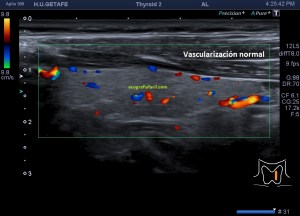

Lo primero, reconoce siempre la normalidad para poder identificar anormalidad. En la imagen 1 tienes una imagen normal de ambos lóbulos tioideos en un corte axial (nos sirve para repasar anatomía básica), en la imagen 2 un corte longitudinal de uno de los lóbulos con su vascularización típica. Bien guarda en tu cabecita estas dos imágenes y ponte en modo concentración para descubrir los cambios semiológicos en el caso de la paciente referida con anterioridad.

2